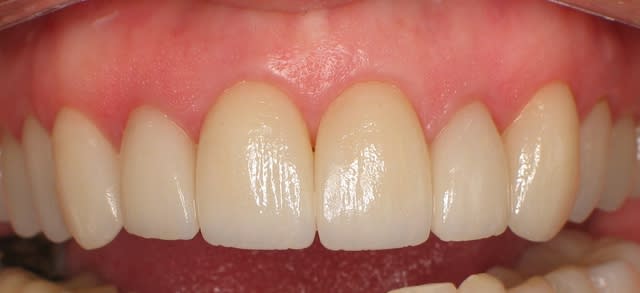

18/11/2010 à 03h25

mince, c'est pas si difficile...

une belle photo avec les couronnes en place, de face, vue complête....

comme celle-ci...

Céramik: super esthétique ton cas! Très top model! Sur un prognathe le challenge est bien plus difficile et je doute qu'avec une connexion vis le porte faux eut été stable dans le temps. Je félicite l'exploit technique de Béotien en tout cas!

pfff!!!! il n'est pas prognathe ton patient

Encore respect! Bravo à toi et au protho le cas était vraiment casse gueule.

Mince la "barre" a été mise haute! pour faire mieux?????

C'était juste un exemple de photo, mieux cadré, pour voir le résultat final, c'est quand même la zone esthétique.

Facettes Empress stratifiées, 6 ans post-op, dame jolie, de 60 ans !

C'est un exemple photo, pas implanto.